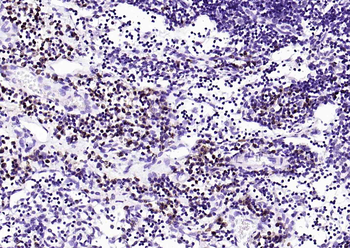

CD7 Rabbit Polyclonal Antibody

CD7

IF, IHC-Fr, IHC-P

应用稀释比例:IHC-P=1:100-500, IHC-F=1:100-500, IF=1:100-500